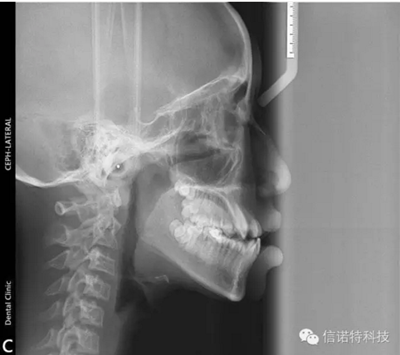

常用X線頭影測量的標(biāo)志點

一、顱部標(biāo)志點

蝶鞍點(S.sella):蝶鞍影像的中心。這是常用的一個顱部標(biāo)志點,在頭顱側(cè)位片上較容易確定。

鼻根點(N.nasion):鼻額縫的最前點。這是前顱部的標(biāo)志點,代表面部與顱部的結(jié)合處。有些X線片上,此點顯示不太清楚,是因為其形態(tài)不規(guī)則骨縫形成角度之故。

耳點(P.porion):外耳道之最上點。頭影測量上常以定位儀耳塞影像之最上點為代表,稱為機械耳點。但也有少數(shù)學(xué)者使用外耳道影像之最上點來代表,則為解剖耳點。

顱底點(Ba.basion):枕骨大孔前緣之中點。一般此點較易確定,常作為后顱底的標(biāo)志。

Bolton點:枕骨髁突后切跡的最凹點。

二、上頜標(biāo)志點

眶點(O.orbitale:)眶下緣之最低點。當(dāng)病人兩側(cè)對稱及在完好的定位下,左右眶點才于同一水平,但實際上難以達到。一般X線片上可顯示左右兩個眶點的影像故常選用兩點之間的點作為眶點,這樣可減小其誤差。

翼上頜裂點(Ptm.pterygomaxillary fissure):翼上頜裂輪廓之最下點。翼上頜裂之前界為上頜竇后壁,后界為蝶骨翼突板之前緣,此標(biāo)志點提供了確定了上頜骨的后界和磨牙的近遠中向間隙及位置的標(biāo)志。

前鼻棘(ANS.anterior nasal spine):前鼻棘之尖。前鼻棘點常作為確定腭平面的兩標(biāo)志點之一,但此標(biāo)志點的清晰與否與X線片的投照條件有關(guān)。一般不作近遠中長度測量所用。

后鼻棘(PNS.posterior nasal spine):硬腭后部骨棘之尖。

上齒槽座點(A.subspinale):前鼻棘與上齒槽緣點間之骨部最凹點。此點僅作為前后向測量所用。

上齒槽緣點(SPr.superior prosthion):上齒槽突之最前下點。此點常在上中切牙之牙釉質(zhì)-牙骨質(zhì)界處。

上中切牙點(UI.upper incisor):上中切牙切緣之最前點。一般上中切牙的測量有兩種方法,一種是以此點與根尖相連作為中上切牙牙長軸來作為角度測量的一個平面,另一種是測量此點與其他結(jié)構(gòu)間的距離。

三、下頜標(biāo)志點

髁頂點(Co.condylion):髁突的最上點。

關(guān)節(jié)點(Ar.articulare):顱底下緣與下頜髁突頸后緣之交點。關(guān)節(jié)點常在髁頂點不易確定時而代替髁頂點。

下頜角點(Go.gonion):下頜角的后下點??赏ㄟ^下頜支平面和下頜平面交角之分角線與下頜角之相交點來確定。

下齒槽座點(B.supramental):下齒槽突緣點與頦前點間之骨部最凹點。齒槽緣點(Id.infradentale):下齒槽突之最前上點。此點常在下中切牙之牙釉質(zhì)-牙骨質(zhì)界處。

下切牙點(Li.lower incisor):下中切牙切緣之最前點。

頦前點(P.pogonion):頦部之最突點。

頦下點(Me.menton):頦部之最下點。

頦頂點(Gn.gnathion):頦前點與頦下點之中點。

D點:下頜體骨性聯(lián)合部之中心點。

這些標(biāo)志點中,有些是在正中矢狀面上,是單個的點。如鼻根點、蝶鞍點等。而有些則是雙側(cè)的點,如下頜角點,關(guān)節(jié)點等。若由于面部不對稱而使兩側(cè)之點不重疊時,則取二點間的中點作為校正的位置。